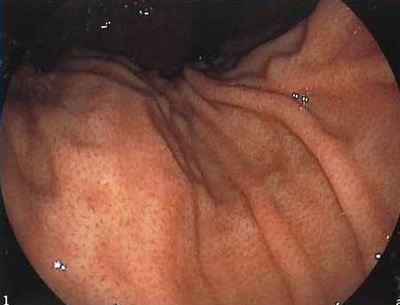

| 正常な胃 | ![]() |

ピロリ菌に感染する前のきれいでなめらかな胃の粘膜 |